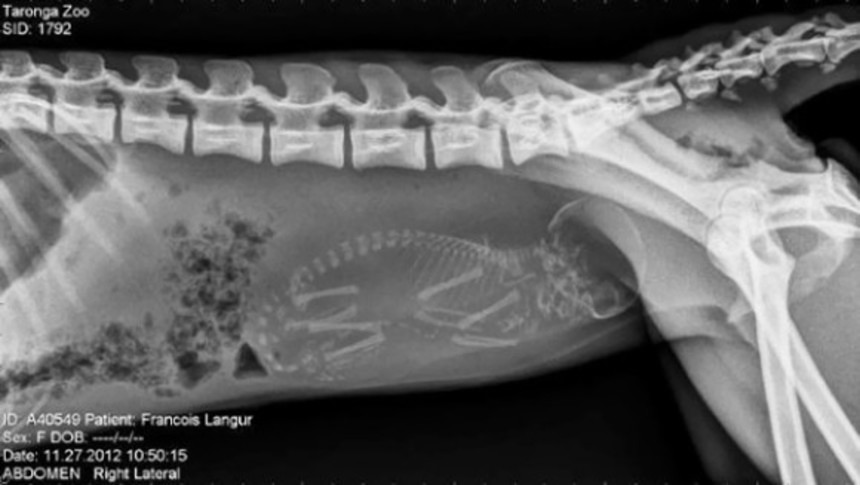

続きを読むさて前回、アラスカンマラミュートの妊娠中のお腹のレントゲン写真を見ていただいたが…